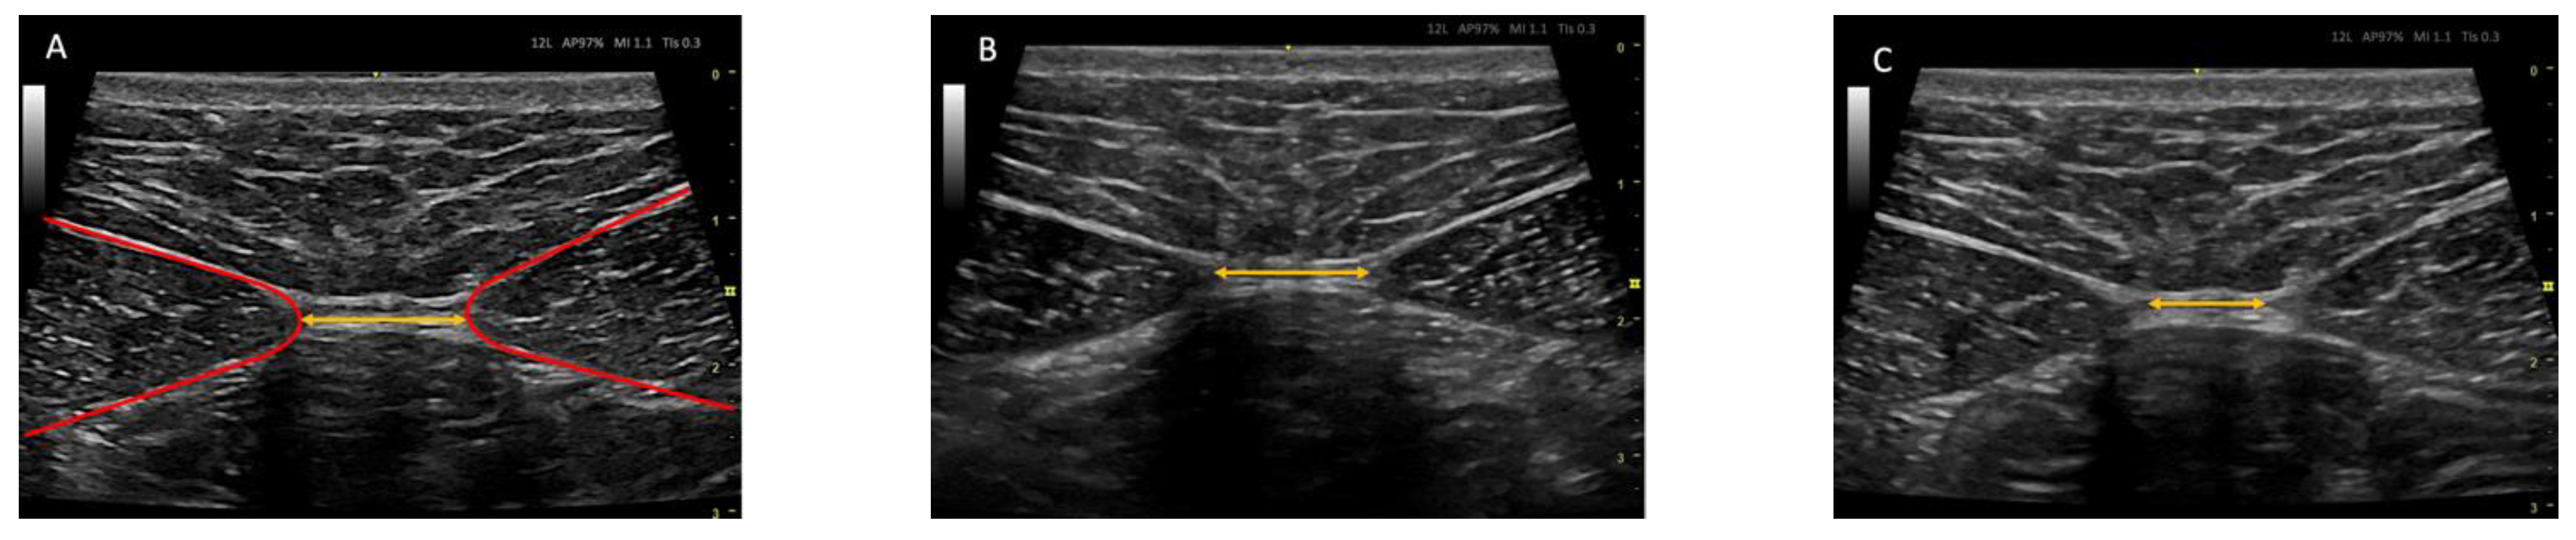

2.7. Ultrasound Protocol

2.8. Outcome Measurements/Descriptive Data